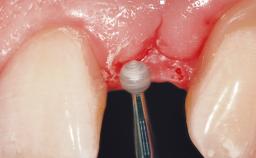

Late Placement of an Implant in a Maxillary Left Central Incisor Site

A 36-year-old female patient was referred for the replacement of the upper left central incisor (tooth 21), which had fractured. Although the tooth had been asymptomatic for many years, the crown began to loosen, at which time she presented to her dentist for an assessment. Teeth 21 and 22 had both been endodontically treated many years previously. She was a healthy individual and a non-smoker.

On examination, the patient had a low lip line and only displayed the coronal half of the anterior teeth when smiling.